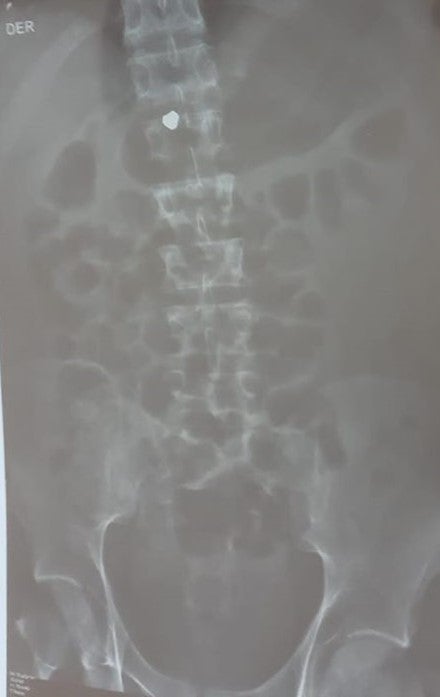

Radiografía donde se observa un perdigón, que se cree que es de plomo, alojado en la médula espinal de Jon Cordero.

Fotografía proporcionada por la familia de Jon Cordero.